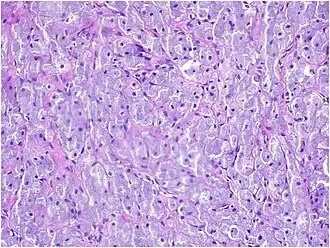

Histopathological Characteristics

Histopathologically, congenital epulis is usually characterized by the presence of big, rounded cells that fill the mucosa's lamina propria and have round to oval nuclei and an abundance of eosinophilic cytoplasm.[10] A thin layer of connective tissue separated the surface layer of cells from the growing new cells. Numerous histological traits, such as a fibrous and granulomatous appearance, have been reported in recent research.[10]

Microscopically, congenital epulis is composed of:

- Sheets of proliferating polygonal to round cells with overlying thin squamous, eosinophilic, granular cytoplasm[12][13]

- Centrally located, round nuclei [7]

These histopathological features are essential in distinguishing congenital epulis from other gingival and soft tissue neoplasms.

Immunohistochemical Analysis

Immunohistochemical staining serves as an important adjunct in the differential diagnosis of congenital epulis.[12] A key feature of congenital epulis is its lack of reaction to the S-100 protein test, which is typically positive in other similar tumors. When doctors examine the tissue using an S-100 stain, congenital epulis does not show a response, unlike other granular cell tumors. This distinction helps confirm the diagnosis and differentiates congenital epulis from other oral tumors in newborns.[6][13]